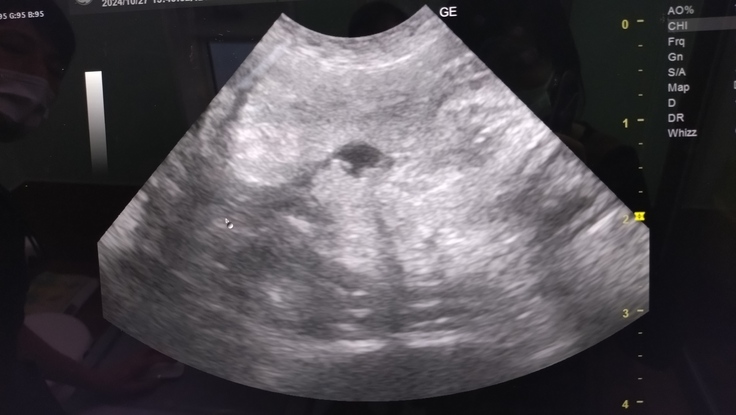

腎盂腎炎疑い一昨日の採血では腎臓肝臓の数値は問題ないので、可能性としては低いが、エコーで見ると拡張してくるので確認。エコー所見で腎盂腎炎はなし。

腹水がまた溜まってる。

エコーの白みはそこまで強くはないが、また腹膜炎が起きている可能性が高い。